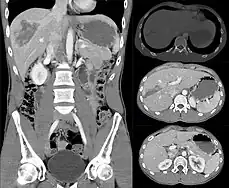

Imaging, such as the use of ultrasound or a computed tomography scan, is the generally preferred way of diagnosis as it is more accurate and is sensitive to bleeding, however; due to logistics this is not always possible.[6] For a person who is hemodynamically unstable a focused assessment with sonography for trauma (FAST) scan may take place which is used to find free floating fluid in the right upper quadrant and left lower quadrant of the abdomen. The FAST scan however may not be indicated in those who are obese and those with subcutaneous emphysema.[7] Its speed and sensitivity to injuries resulting in 400mL of free-floating fluid make it a valuable tool in the evaluation of unstable persons. Computed tomography is another diagnostic study which can be performed, but typically is only used in those who are hemodynamically stable.[7] A physical examination may be used but is typically inaccurate in blunt trauma, unlike in penetrating trauma where the trajectory the projectile took can be followed digitally.[8] A diagnostic peritoneal lavage (DPL) may also be utilized but has limited application as it is hard to determine the origin of the bleeding.[9] A diagnostic peritoneal lavage is generally discouraged when FAST is available as it is invasive and non-specific.[7]

Liver injuries are classified on a Roman numeral scale with I being the least severe, to V being the most severe, according to the AAST (American Association for the Surgery of Trauma) liver injury scale.[10]